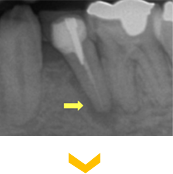

根管内に残っていた破折した金属リーマー。顕微鏡による的確に除去できた症例。

根管内に残っていた破折した金属リーマー。顕微鏡による的確に除去できた症例。

矢印の先に金属片状の不透過象が認められる。根尖に感染炎症による透過像を認める。

矢印の先に金属片状の不透過象が認められる。根尖に感染炎症による透過像を認める。

根管内の感染源と共に除去された。

根管内の感染源と共に除去された。

根管治療終了後。炎症症状は無くなり、骨の回復も認められる。

根管治療終了後。炎症症状は無くなり、骨の回復も認められる。